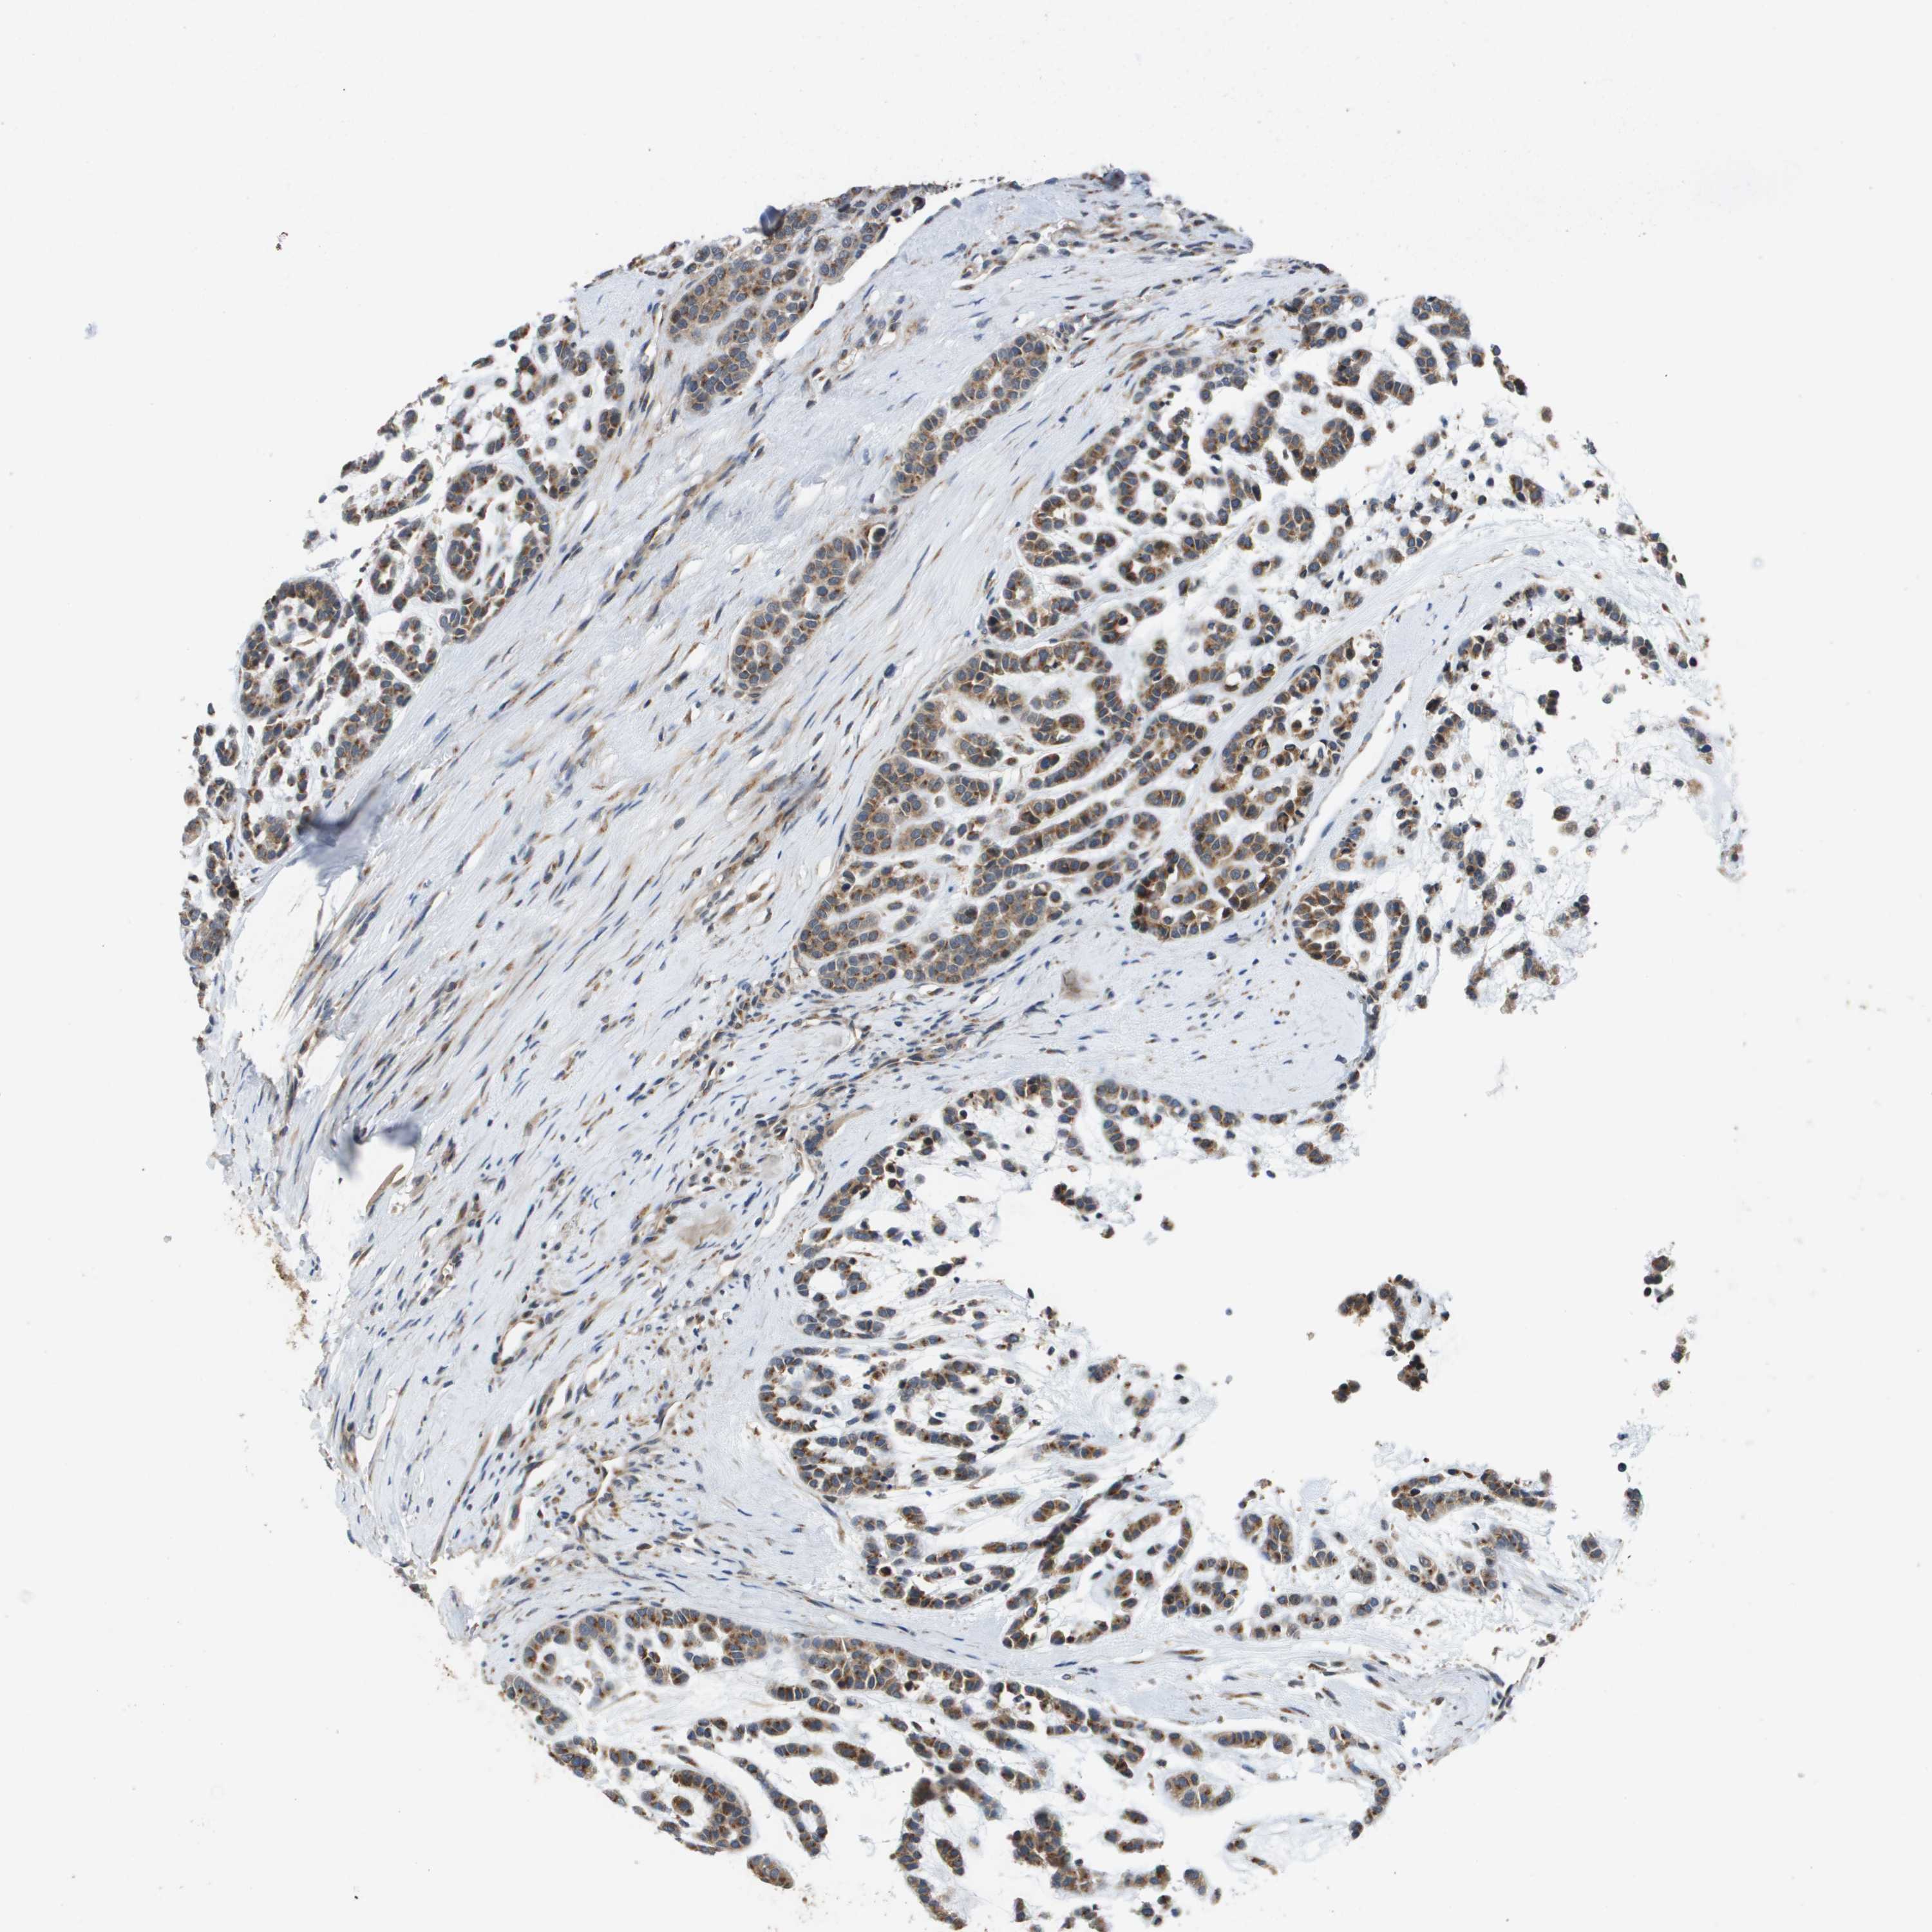

HEAD AND NECK CANCER - Protein expressioni

A mouse-over function shows sample information and annotation data. Click on an image to view it in a full screen mode. Samples can be filtered based on level of antibody staining by selecting one or several of the following categories: high, medium, low and not detected. The assay and annotation is described here.

Antibody stainingi

Antibody staining in the annotated cell types in the current human tissue is reported as not detected, low, medium, or high, based on conventional immunohistochemistry profiling in selected tissues. This score is based on the combination of the staining intensity and fraction of stained cells.

Each image is clickable and will lead to virtual microscopy that enables deeper exploration of all samples and also displays staining intensity scores, fraction scores and subcellular localization as well as patient and tissue information for each sample.

Antibody HPA006277

Antibody HPA006507

Antibody CAB017027

Staining

High

Medium

Low

Not detected

Intensity

Strong

Moderate

Weak

Negative

Quantity

>75%

75%-25%

<25%

None

Location

Nuclear

Cytoplasmic/membranous

Cytoplasmic/membranous,nuclear

Squamous cell carcinoma, NOS

Carcinoma, NOS

Adenocarcinoma, NOS

Squamous cell carcinoma, metastatic, NOS

Adenoma, NOS